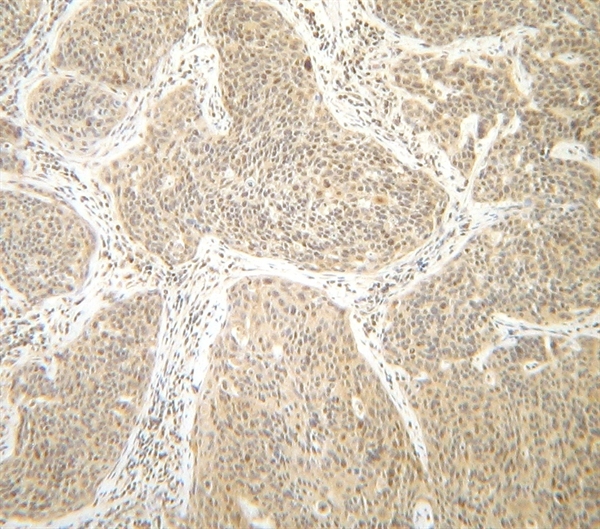

(Staining of formalin fixed, paraffin embedded human cervical squamous cell carcinoma with Rabbit anti Human interferon-gamma following heat mediated antigen retrieval using sodium citrate buffer (pH6.0))